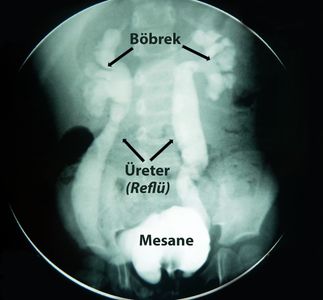

İdrar kesesindeki (mesane) idrarın yukarı idrar yollarına kaçmasına vesikoüreteral reflü denir. Normalde işerken idrar yalnızca dışarı çıkmalıdır. İdrarın yukarı idrar yollarına kaçması, her ne sebeple olursa olsun anormal bir durumdur.